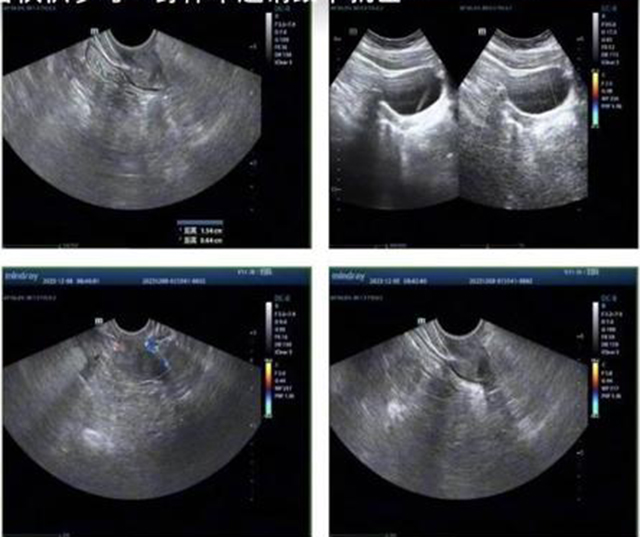

Bài viết của Tiểu Nguyệt được rất nhiều người chú ý, thậm chí có cả các bác sĩ chuyên về sản phụ khoa. Cô gái trẻ bắt đầu lo lắng và quyết định tự đến bệnh viện kiểm tra. Thật không ngờ, kết quả chỉ ra tử cung của cô chỉ lớn hơn hạt đậu nành một chút - một kích thước nhỏ hơn cả tử cung trung bình của trẻ sơ sinh. Trong khi tử cung bình thường ở phụ nữ trưởng thành dài khoảng 7.5cm, rộng 5cm, dày 2.5cm thì tử cung của Tiểu Nguyệt chỉ khoảng 13mm x 5mm x 19mm.

Đáng nói là trong lần siêu âm đầu tiên, bác sĩ không thể nhìn thấy lớp nội mạc tử cung - nơi trứng đã thụ tinh cần bám vào để làm tổ. Khi ấy, bác sĩ nói thẳng: nếu không có nội mạc tử cung, nghĩa là khả năng mang thai bằng phương pháp tự nhiên gần như bằng 0. Nghe tới đây, Tiểu Nguyệt òa khóc nức nở. Cô mới chỉ 21 tuổi, còn chưa có bạn trai, chưa từng nghĩ đến chuyện con cái, nhưng giờ đây lại phải đối mặt với nguy cơ không thể làm mẹ.

May mắn thay, ở lần siêu âm thứ hai, lớp nội mạc tử cung dù rất mỏng cũng đã mơ hồ hiện lên. Điều đó đồng nghĩa với việc vẫn còn hy vọng. Tuy nhiên, quá trình điều trị sẽ rất dài và gian nan. Cụ thể Tiểu Nguyệt sẽ phải dùng thuốc nội tiết để kích thích tử cung phát triển, nâng cao nồng độ estrogen và chờ đợi từng bước tiến triển nhỏ nhất. Ngay cả khi tử cung đạt đến mức có thể mang thai, cô vẫn phải đối mặt với nguy cơ sảy thai, sinh non hoặc vô sinh thứ phát.

Dù đã 21 tuổi nhưng tử cung của Tiểu Nguyệt chỉ lớn hơn hạt đậu nành một chút, rất khó mang thai (Ảnh từ bài đăng của nhân vật)